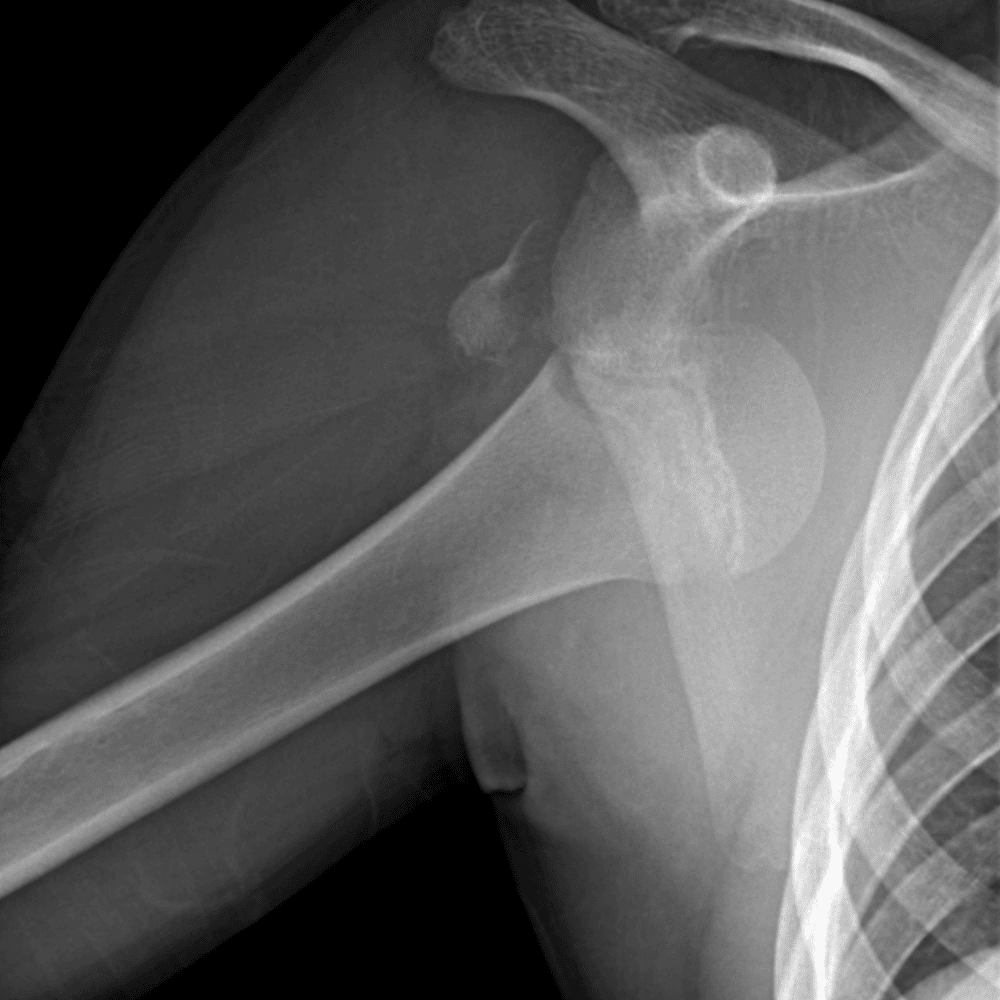

Simuliert den Dienst durch subtile oder schwierige Fälle und einige Normalbefunde.

30 Fälle